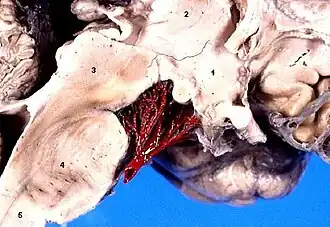

1:Hipotálamo. 2:Tálamo. 3:Mesencéfalo. 4:Protuberancia. 5:Médula espinal.